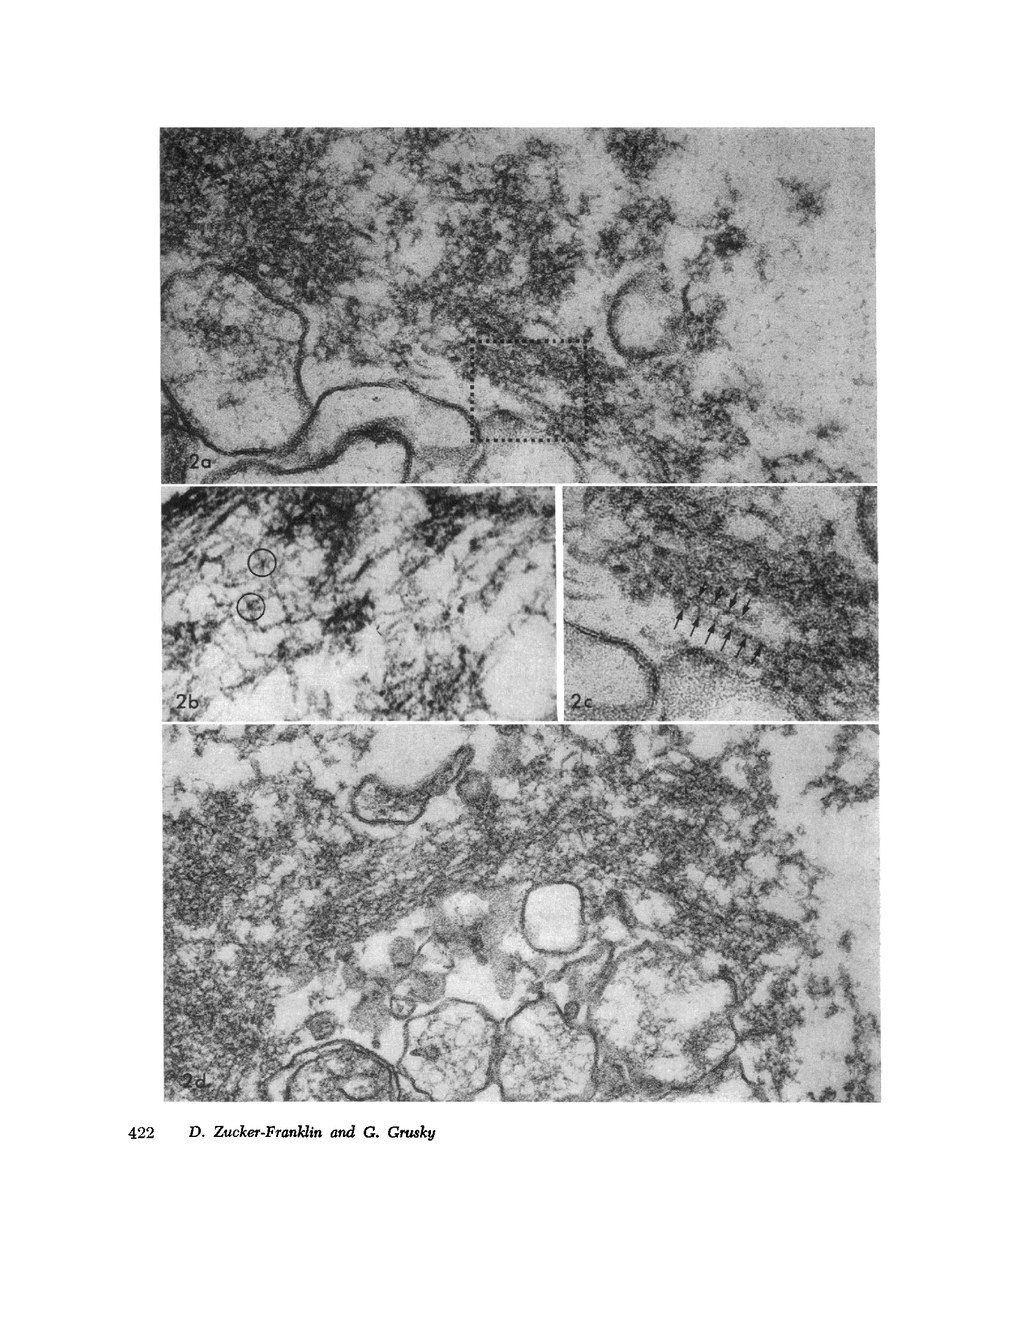

The contractility of platelets has been attributed to an actomyosin-like protein which has been well defined on a physicochemical basis. Moreover, platelets contain ±80 A filaments which resemble actin filaments in smooth muscle. Studies were undertaken on human and bovine platelets to better define the morphologic structures which may subserve this contractile function. In order to identify actin, the ability of the filaments to react with heavy meromyosin (HMM) was tested. Accordingly, platelets were glycerinated and treated with HMM. In addition, platelet actin was extracted, reacted with HMM, and examined by negative staining. In both instances typical arrowhead structures with clearly defined polarity and a periodicity of ±360 A formed. As is the case with purified muscle actin, the complexes were dissociable with Mg-ATP. The formation of myosin-like filaments was observed when osmotically shocked platelets were incubated with MgCl2 and excess ATP. These “thick” filaments measured 250-300 A in width, tapered at both ends and often occurred in clumps. They resembled aggregates of thick filaments described in contracted smooth muscle. Extraction of platelets by methods suitable for the demonstration of myosin showed filaments with an average length of 0.3 μ, a smooth shaft, and frayed or bulbous ends. These appeared identical to those seen in synthetically prepared myosin of striated muscle. It is suggested that the filaments described here represent the actin and myosin of platelets.